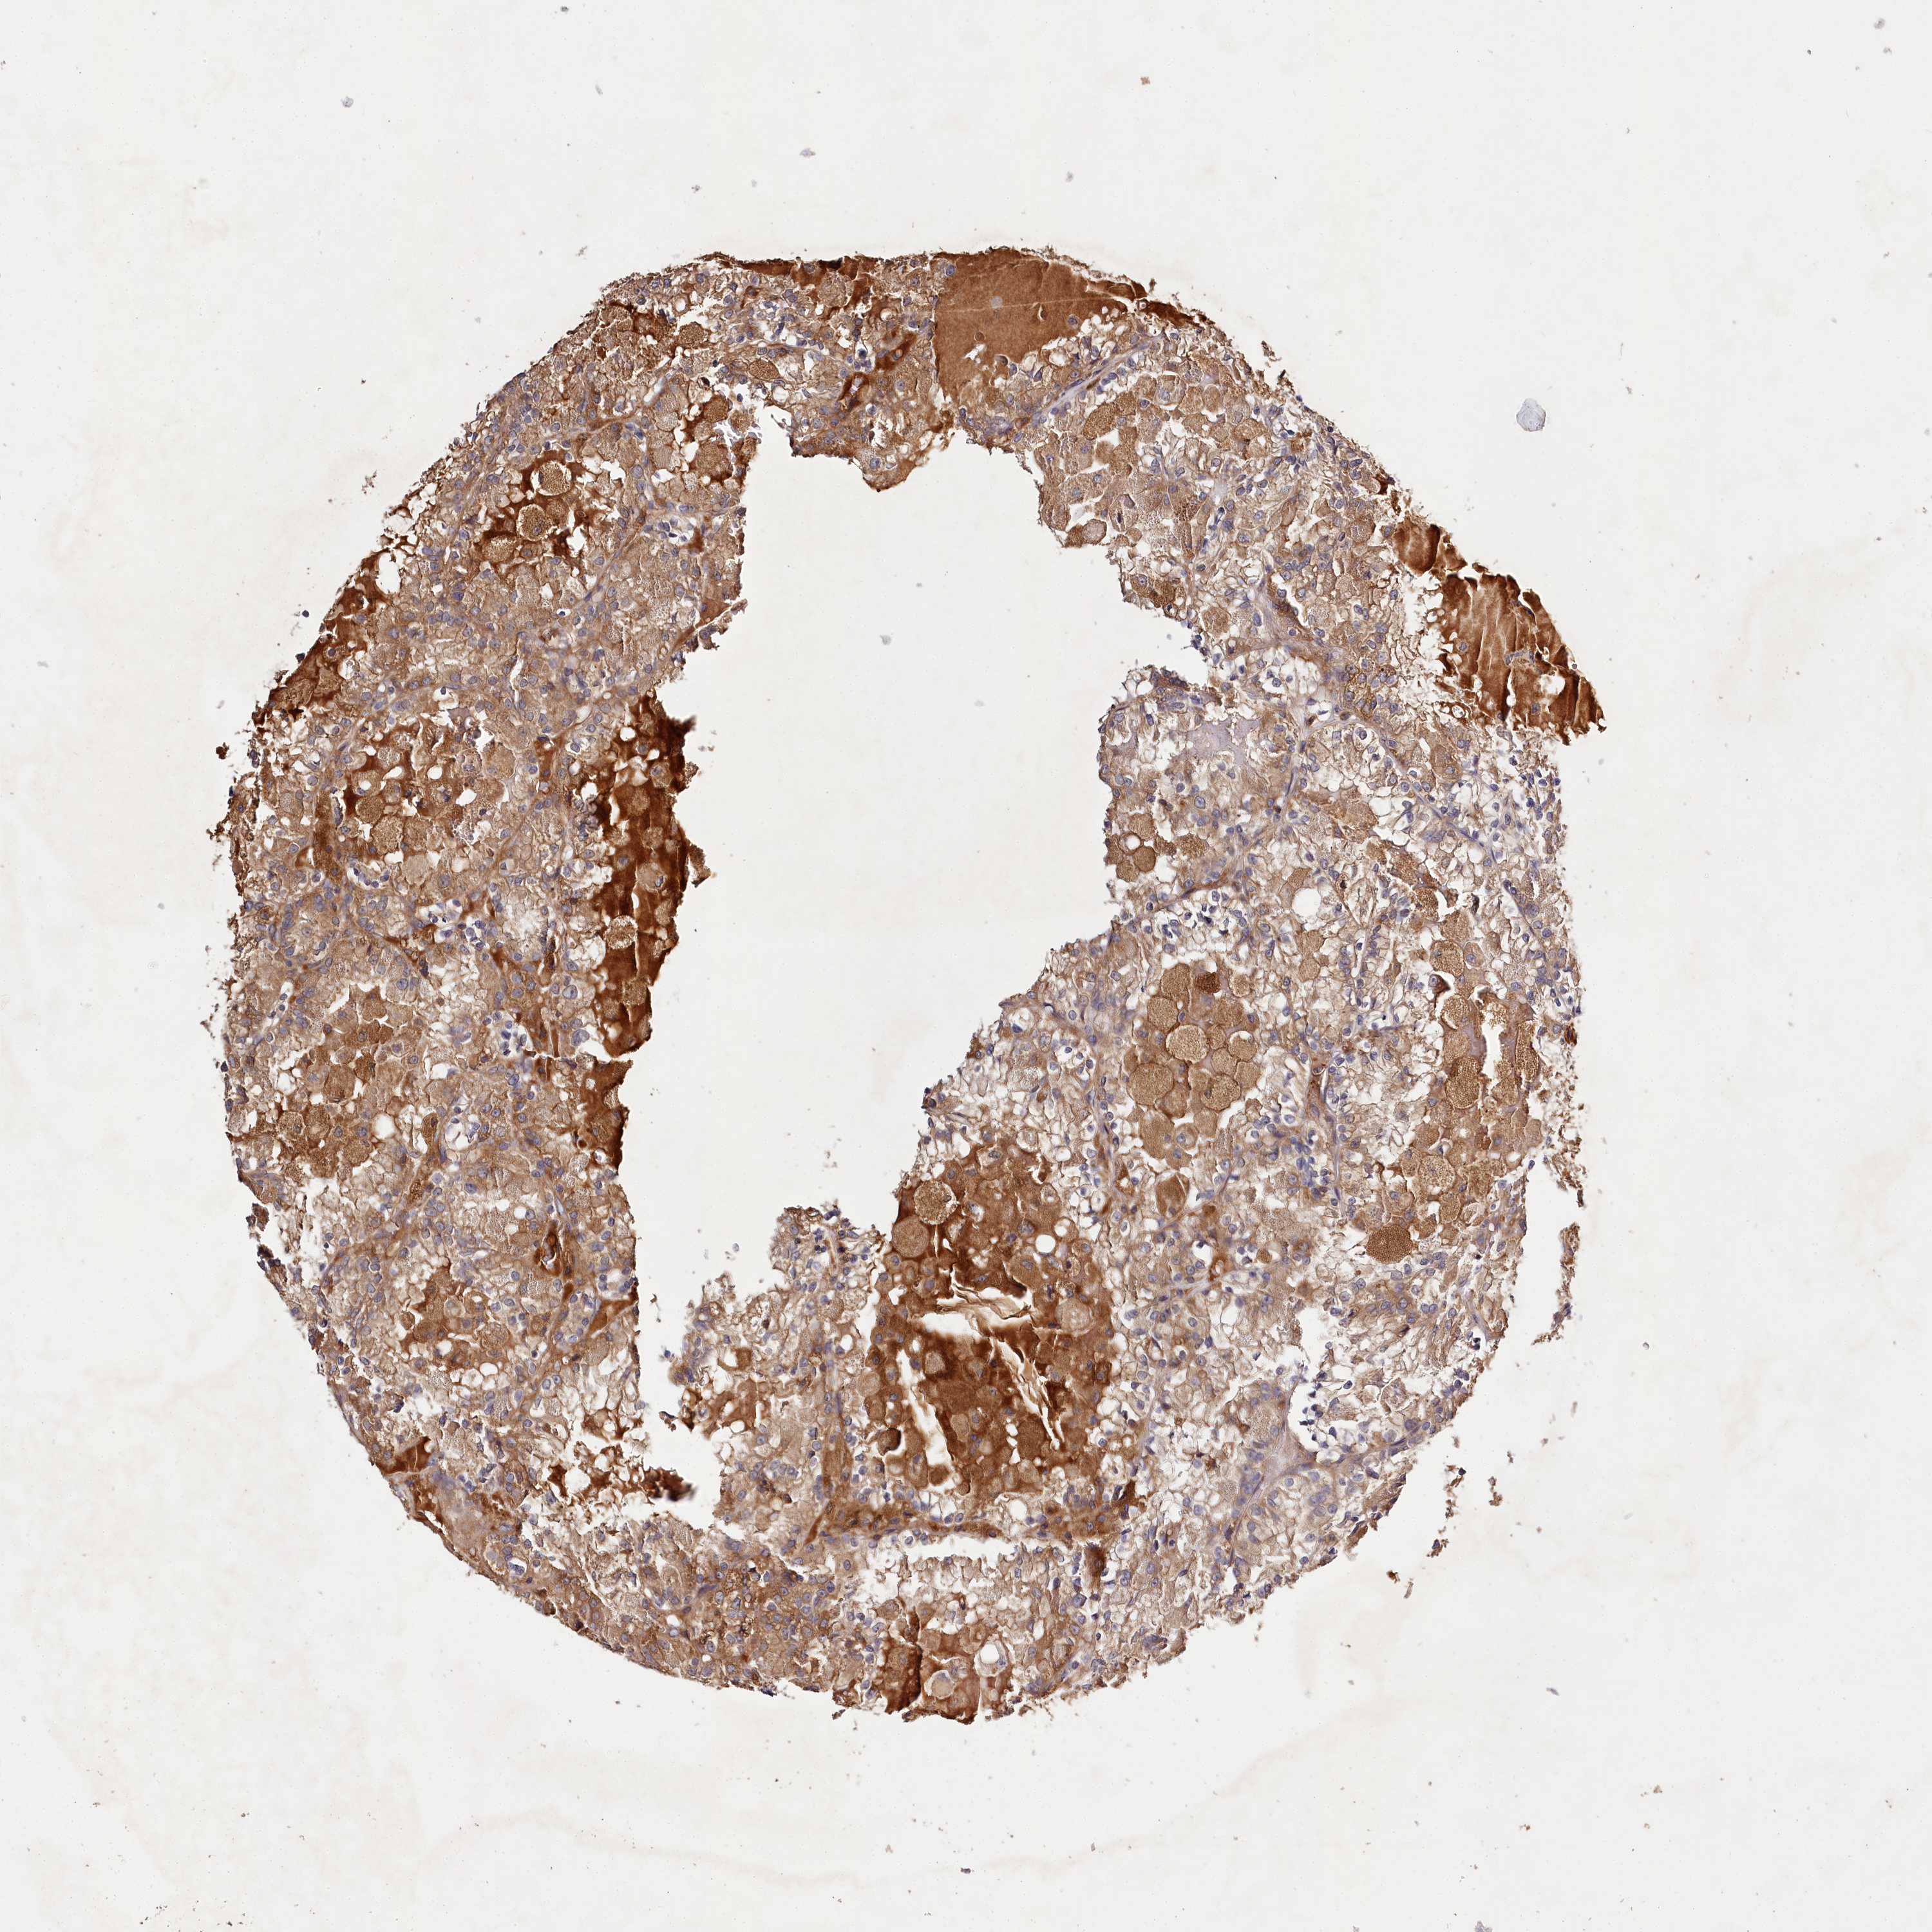

KIDNEY RENAL PAPILLARY CELL CARCINOMA (TCGA) - Interactive survival scatter ploti

The Survival Scatter plot shows the clinical status (i.e. dead or alive) for all individuals in the patient cohort, based on the same data that underlies the corresponding Kaplan-Meier plots. Patients that are alive at last time for follow-up are shown in blue and patients who have died during the study are shown in red.

The x-axis shows the expression levels (FPKM) of the investigated gene in the tumor tissue at the time of diagnosis. The y-axis shows the follow-up time after diagnosis (years). Both axes are complimented with kernel density curves demonstrating the data density over the axes. The top density plot shows the expression levels (FPKM) distribution among dead (red) and alive patients (blue). The right density plot shows the data density of the survived years of dead patients with high and low expression levels respectively, stratified using the cutoff indicated by the vertical dashed line through the Survival Scatter plot. This cutoff is automatically defined based on the FPKM cutoff that minimizes the p-score. The cutoff can be changed by dragging the vertical line or by entering a cutoff value in the square labeled "Current cut-off".

Under the Survival Scatter plot the p-score landscape (black curve; left axis) is shown together with dead median separation (red curve; right axis). Dead median separation is the difference in median mRNA expression between patients who have died with high and low expression, respectively. It is calculated as follows: median FPKM expression of dead patients with high expression - median FPKM expression of dead patients with low expression. This is intended to aid the user in visually exploring custom cutoffs and the associated p-scores and dead median separation.

Individual patient data is displayed and can be filtered by clicking on one or more of the category buttons on the top of the page. Categories describing expression level and patient information include: high, low, alive, dead, female, male and tumor stages. The scale of the x-axis can be toggled between linear and log-scale by clicking on the "x log" button. Mouse-over function shows TCGA ID, patient information and mRNA expression (FPKM) for each patient.

& Survival analysisi

Kaplan-Meier plots summarize results from analysis of correlation between mRNA expression level and patient survival. Patients were divided based on level of expression into one of the two groups "low" (under cut off) or "high" (over cut off). X-axis shows time for survival (years) and y-axis shows the probability of survival, where 1.0 corresponds to 100 percent.

LSS is not prognostic in Kidney Renal Papillary Cell Carcinoma (TCGA)